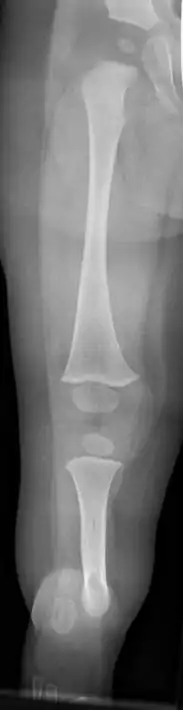

![]() | |

| Fibula hemimelia in patient affecting right side | |